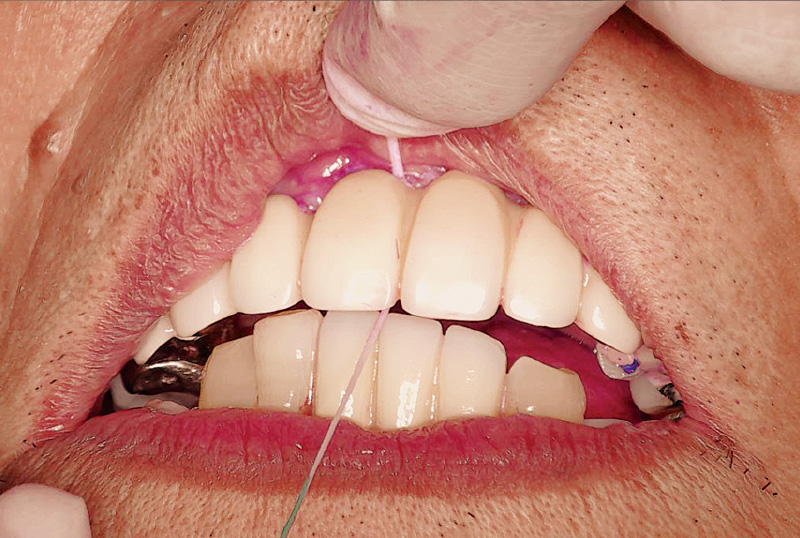

症例の患者さんは、初診時74歳の男性です(図1, 2)。この時は、別の一眼レフカメラで撮影していますが、現在は初診時の5枚法写真は全て歯科衛生士が「ルナビューショット」で撮影しています。一眼レフカメラは女性にとっては少し重たいですし、ミラーを持ちながら片手で撮影するには、ある程度の技術が必要です。また、患者さんにお見せするためパソコンにインポートする際にも一手間が必要です。「ルナビューショット」はとにかく簡単、手軽に撮影でき、「TrinityCore Pro」と連携して、ミラーモードも気にせず自動配置してくれます。オペの様子もアシストする歯科衛生士が随時撮影して、オペ後に患者さんにお見せしながら処置内容を説明しています。

図1 初診時74歳男性。₆の脱離を主訴に来院された。歯を残すことを希望され、前歯部はブリッジ、臼歯部には義歯治療を行った。(一眼レフカメラにて撮影) -